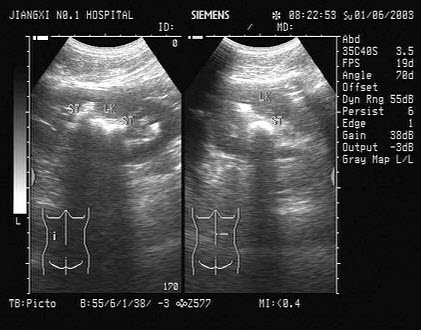

10、单项选择题

男、30岁,体检时发现脾门处光团,根据超声声像图诊断为()

A.副脾

B.淋巴结

C.转移癌

D.脾脓肿

E.左肾上腺肿瘤

18、单项选择题

女性,41岁,有阵发性高血压病史,超声检查如图所示,该病例最可能诊断()

A.腺瘤

B.肾脏肿瘤

C.嗜络细胞瘤

D.髓样脂肪瘤

E.肾上腺转移瘤